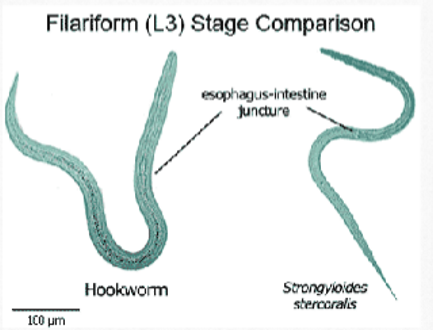

rhabditiform vs filariform

strongyloides stercoralis filariform larvae

esophagus extends to 40% of the body length

Focus carefully to notice the notched tail

Length of esophagus and the notch in the tail allow you to distinguish between the two larval forms

The esophagus does not have a bulb

strongyloides rhab vs filariform

rhabditiform: short buccal cavity; esophageal bulb; pointed tail; large genital primoridum

filariform: short buccal cavity; no esophageal bulb; notched tail

hookworm rhab vs filariform

rhabditiform: long buccal cavity; esophageal bulb; straight tail; small genital primordium

filariform: long buccal cavity; no esophageal bulb; pointed tail

strongyloides rhab vs hookworm rhab

strongyloides: short buccal cavity; esophageal bulb; pointed tail

hookworm: long buccal cavity; esophageal bulb; straight tail

strongyloides filariform vs hookworm filariform

strongyloides: short buccal cavity; no esophageal bulb; notched tail

hookworm: long buccal cavity; no esophageal bulb; pointed tail